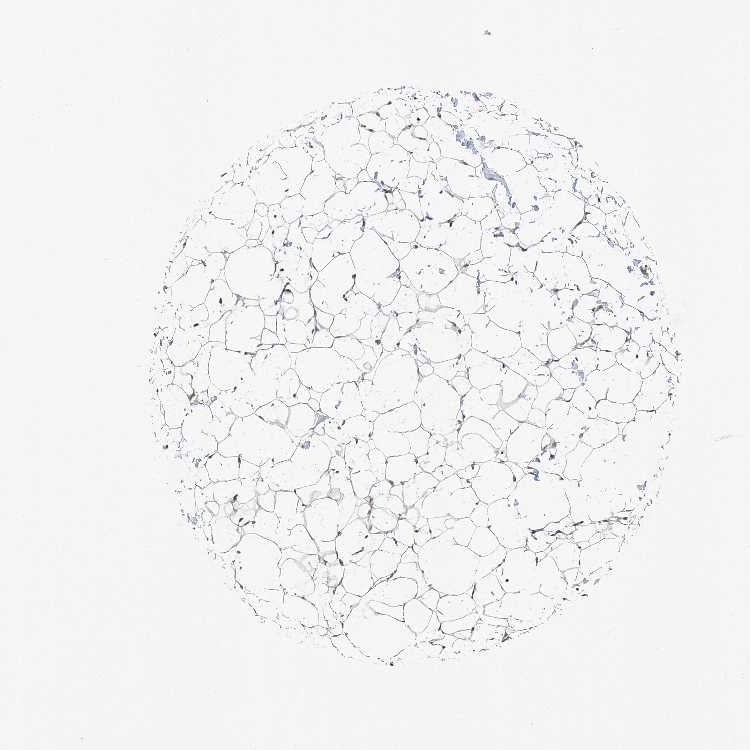

SOFT TISSUE 1 - Antibody stainingi

Antibody staining in the annotated cell types in the current human tissue is reported as not detected, low, medium, or high, based on conventional immunohistochemistry profiling in selected tissues. This score is based on the combination of the staining intensity and fraction of stained cells.

Each image is clickable and will lead to virtual microscopy that enables deeper exploration of all samples and also displays staining intensity scores, fraction scores and subcellular localization as well as patient and tissue information for each sample.

Antibody HPA028220

Fibroblasts Low

SOFT TISSUE 2 - Antibody stainingi

Chondrocytes Medium